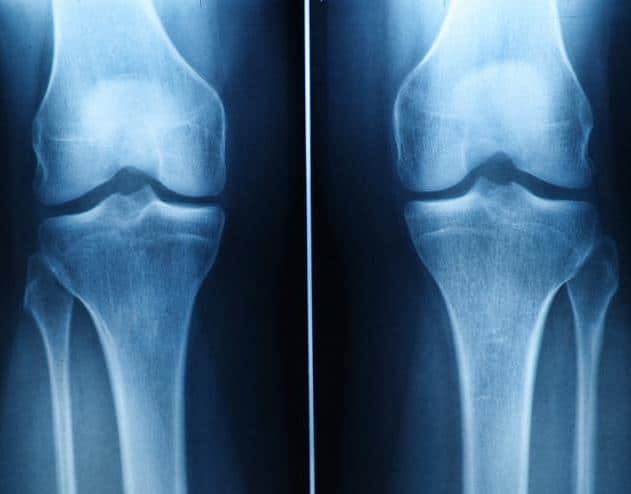

Limited Regenerative Capacity of Cartilage

Cartilage has limited regenerative capacity, and current pharmacological treatments offer only symptomatic relief. Patients who don’t respond to conventional therapies may undergo surgical procedures like arthroplasty or total joint replacement.